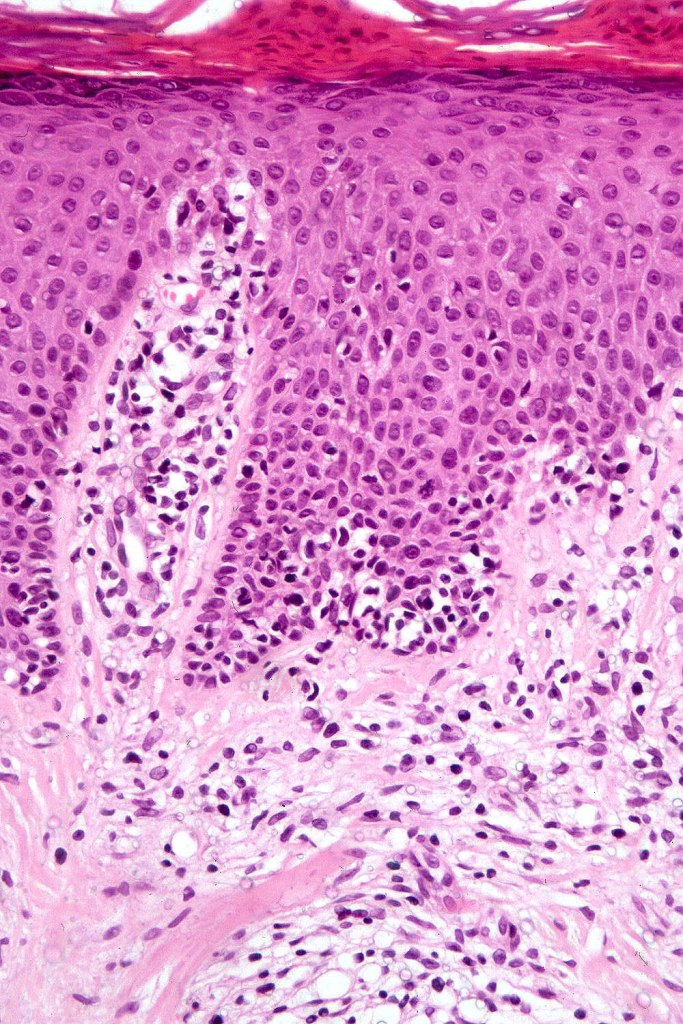

Histological features

The histological hallmark of mycosis fungoides is the presence of large atypical lymphocytes with a convoluted/cerebriform nuclear border (Sézary cells). These may be found at the epidermal-dermal jnuction and as collections within the epidermis (Pautrier microabscess). These are most easily found in plaque stage disease. The epidermal component can be subtle in patch stage disease and is often lost in tumor stage dsease. The classification into patch, plaque & tumor stage disease is less helpful histologically as the features merge from one to the other. It is all a matter of degree.

Plaque Stage Disease

•Compact hyperkeratosis & patchy parakeratosis

•Acanthosis

•Psoriasiform hyperplasia common

•Epidermotropism is often marked with conspicuous Pautrier microabscesses

•Lichenoid variant & poikiloderma atrophicans vasculare

•Variable folliculotropism (+/- mucinosis) & syringotropism

•Coarse collagen bundles in papillary dermis

•Superficial band-like dermal infiltrate of atypical lymphocytes, eosinophils, plasma cells & histiocytes